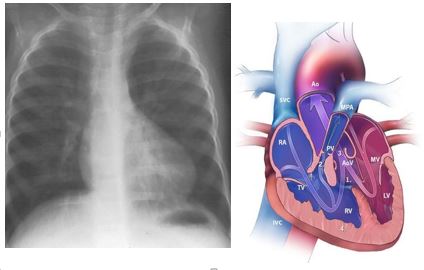

Σε αυτήν, τα ευρήματα του Echo καρδιάς είναι:

• Απόφραξη του χώρου εξόδου της δεξιάς κοιλίας(RVOTO), λόγω υπερτροφίας του infundibular

• Εφφιπεύουσα αορτή

• Μεσοκοιλιακή επικοινωνία &

• Υπερτροφία της δεξιάς κοιλίας

Ακτινογραφία θώρακα η απεικόνιση της καρδιάς ως «Γαλλική μπότα».